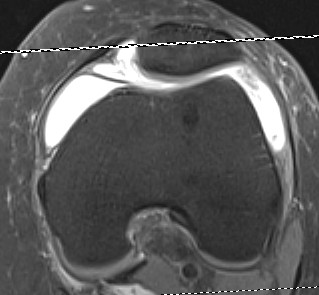

MRI